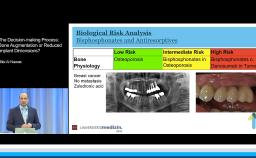

This lecture analyzes the impact of key risk factors on esthetic outcomes with implant restorations in the anterior maxilla. It provides a standardized way of collecting pertinent clinical and radiographic data and presenting them to the patient in order to form realistic treatment expectations. This presentation stresses the importance of prosthodontically driven implant positioning by respecting the ‘comfort zones’ and avoiding the ‘danger zones’. It recommends practical chairside procedures for shaping natural emergence profiles with the help of provisional implant restorations and then conveying this information to the dental laboratory by fabricating customized impression copings. Finally, this lecture stresses the importance of original-on-original components to avoid future mechanical and biological complications.

- identify risk factors in the management of patients with anterior maxillary tooth loss